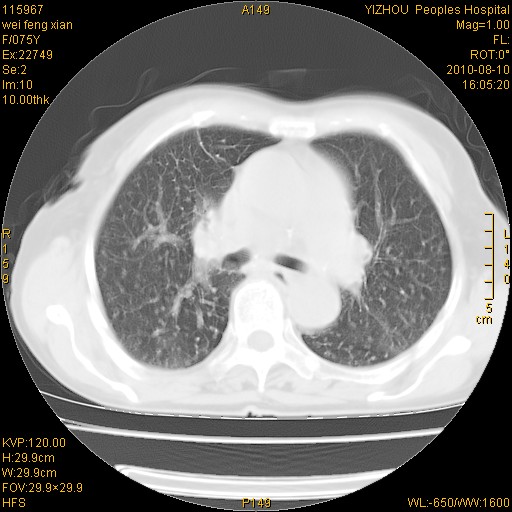

标题: CT28313:两肺弥漫性病变

女,75岁,患者反复头昏乏力面色苍白3年,再发10天入院。临床贫血查因。

双肺间质增生并右肺上叶炎性改变,不除外右肺上叶结核病肺内播散

考虑右肺上叶炎症合并双肺结核可能性大,建议上传纵隔窗ct图片。

双肺结核可能性大

考虑尘肺并结核;右上肺支气管扩张!

结核、尘肺、支气管肺泡癌都不能除外

右肺上叶继发性肺结核伴肺内血型播散!

考虑右肺上叶继发性肺结核伴两肺播散。